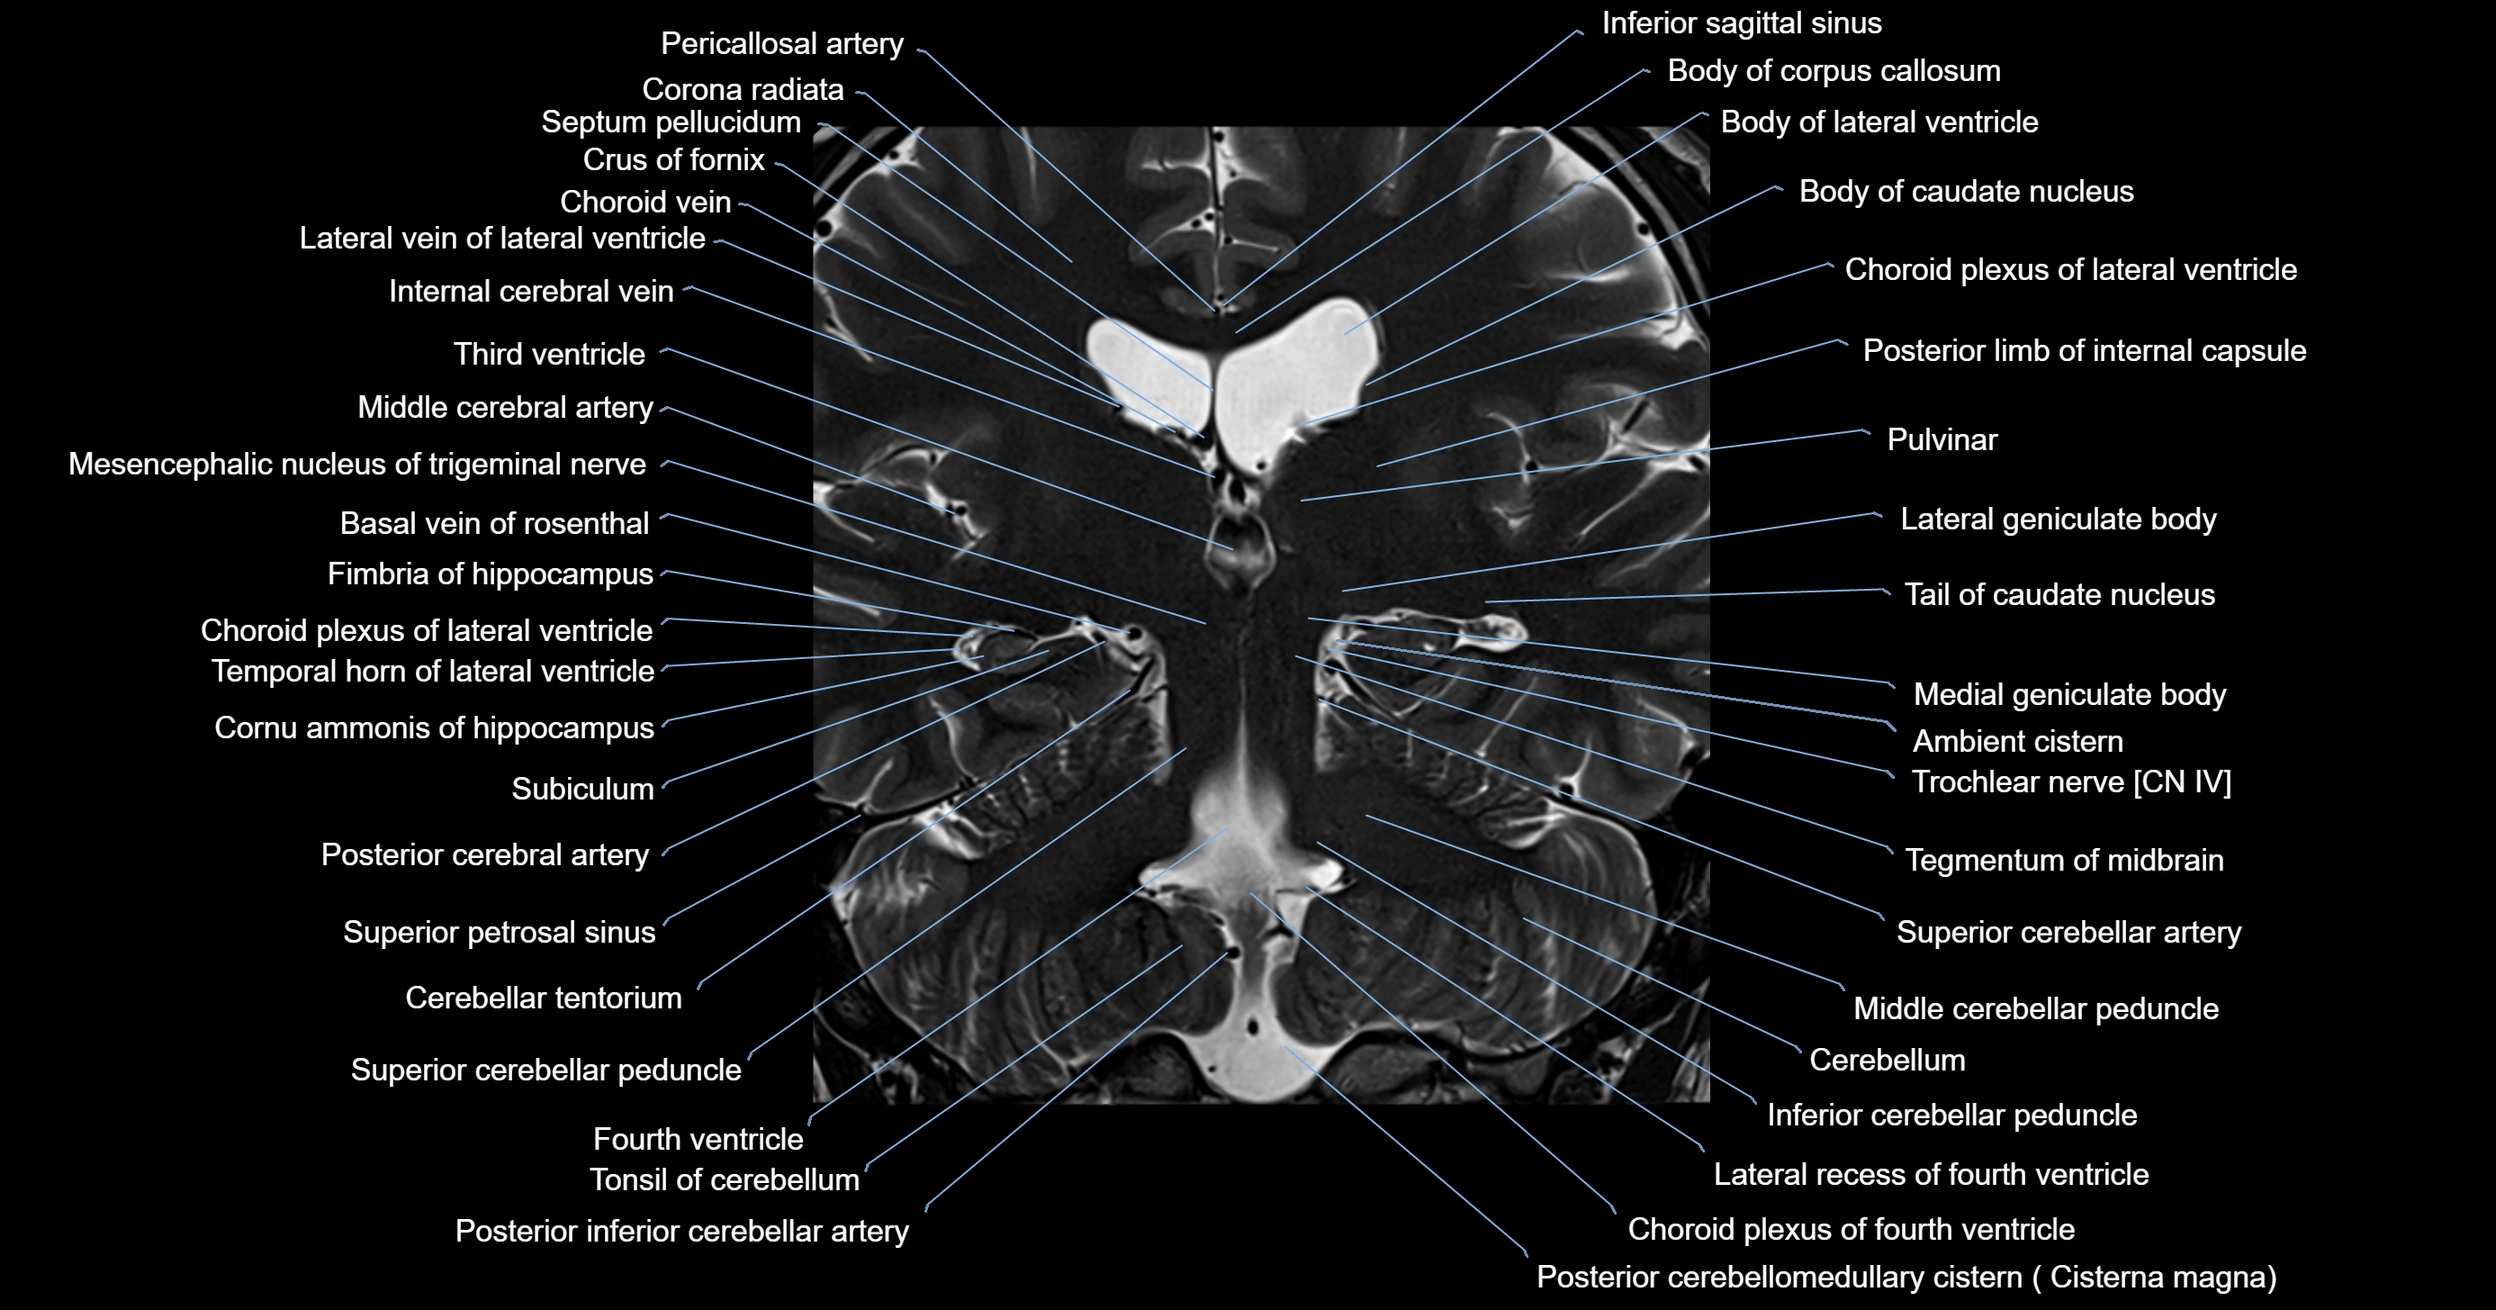

- Ambient cistern

- Basal vein of rosenthal

- Cerebellum

- Choroid plexus of fourth ventricle

- Choroid plexus of the lateral ventricle

- Inferior cerebellar peduncle

- Lateral geniculate body

- Medial geniculate body

- Middle cerebellar peduncle

- Posterior cerebellomedullary cistern (cisterna magna)

- Pulvinar

- Superior cerebellar artery

- Superior cerebellar peduncle

- Superior petrosal sinus

- Tegmentum of midbrain

- Tonsil of cerebellum

- Trochlear nerve (Cranial nerve IV)